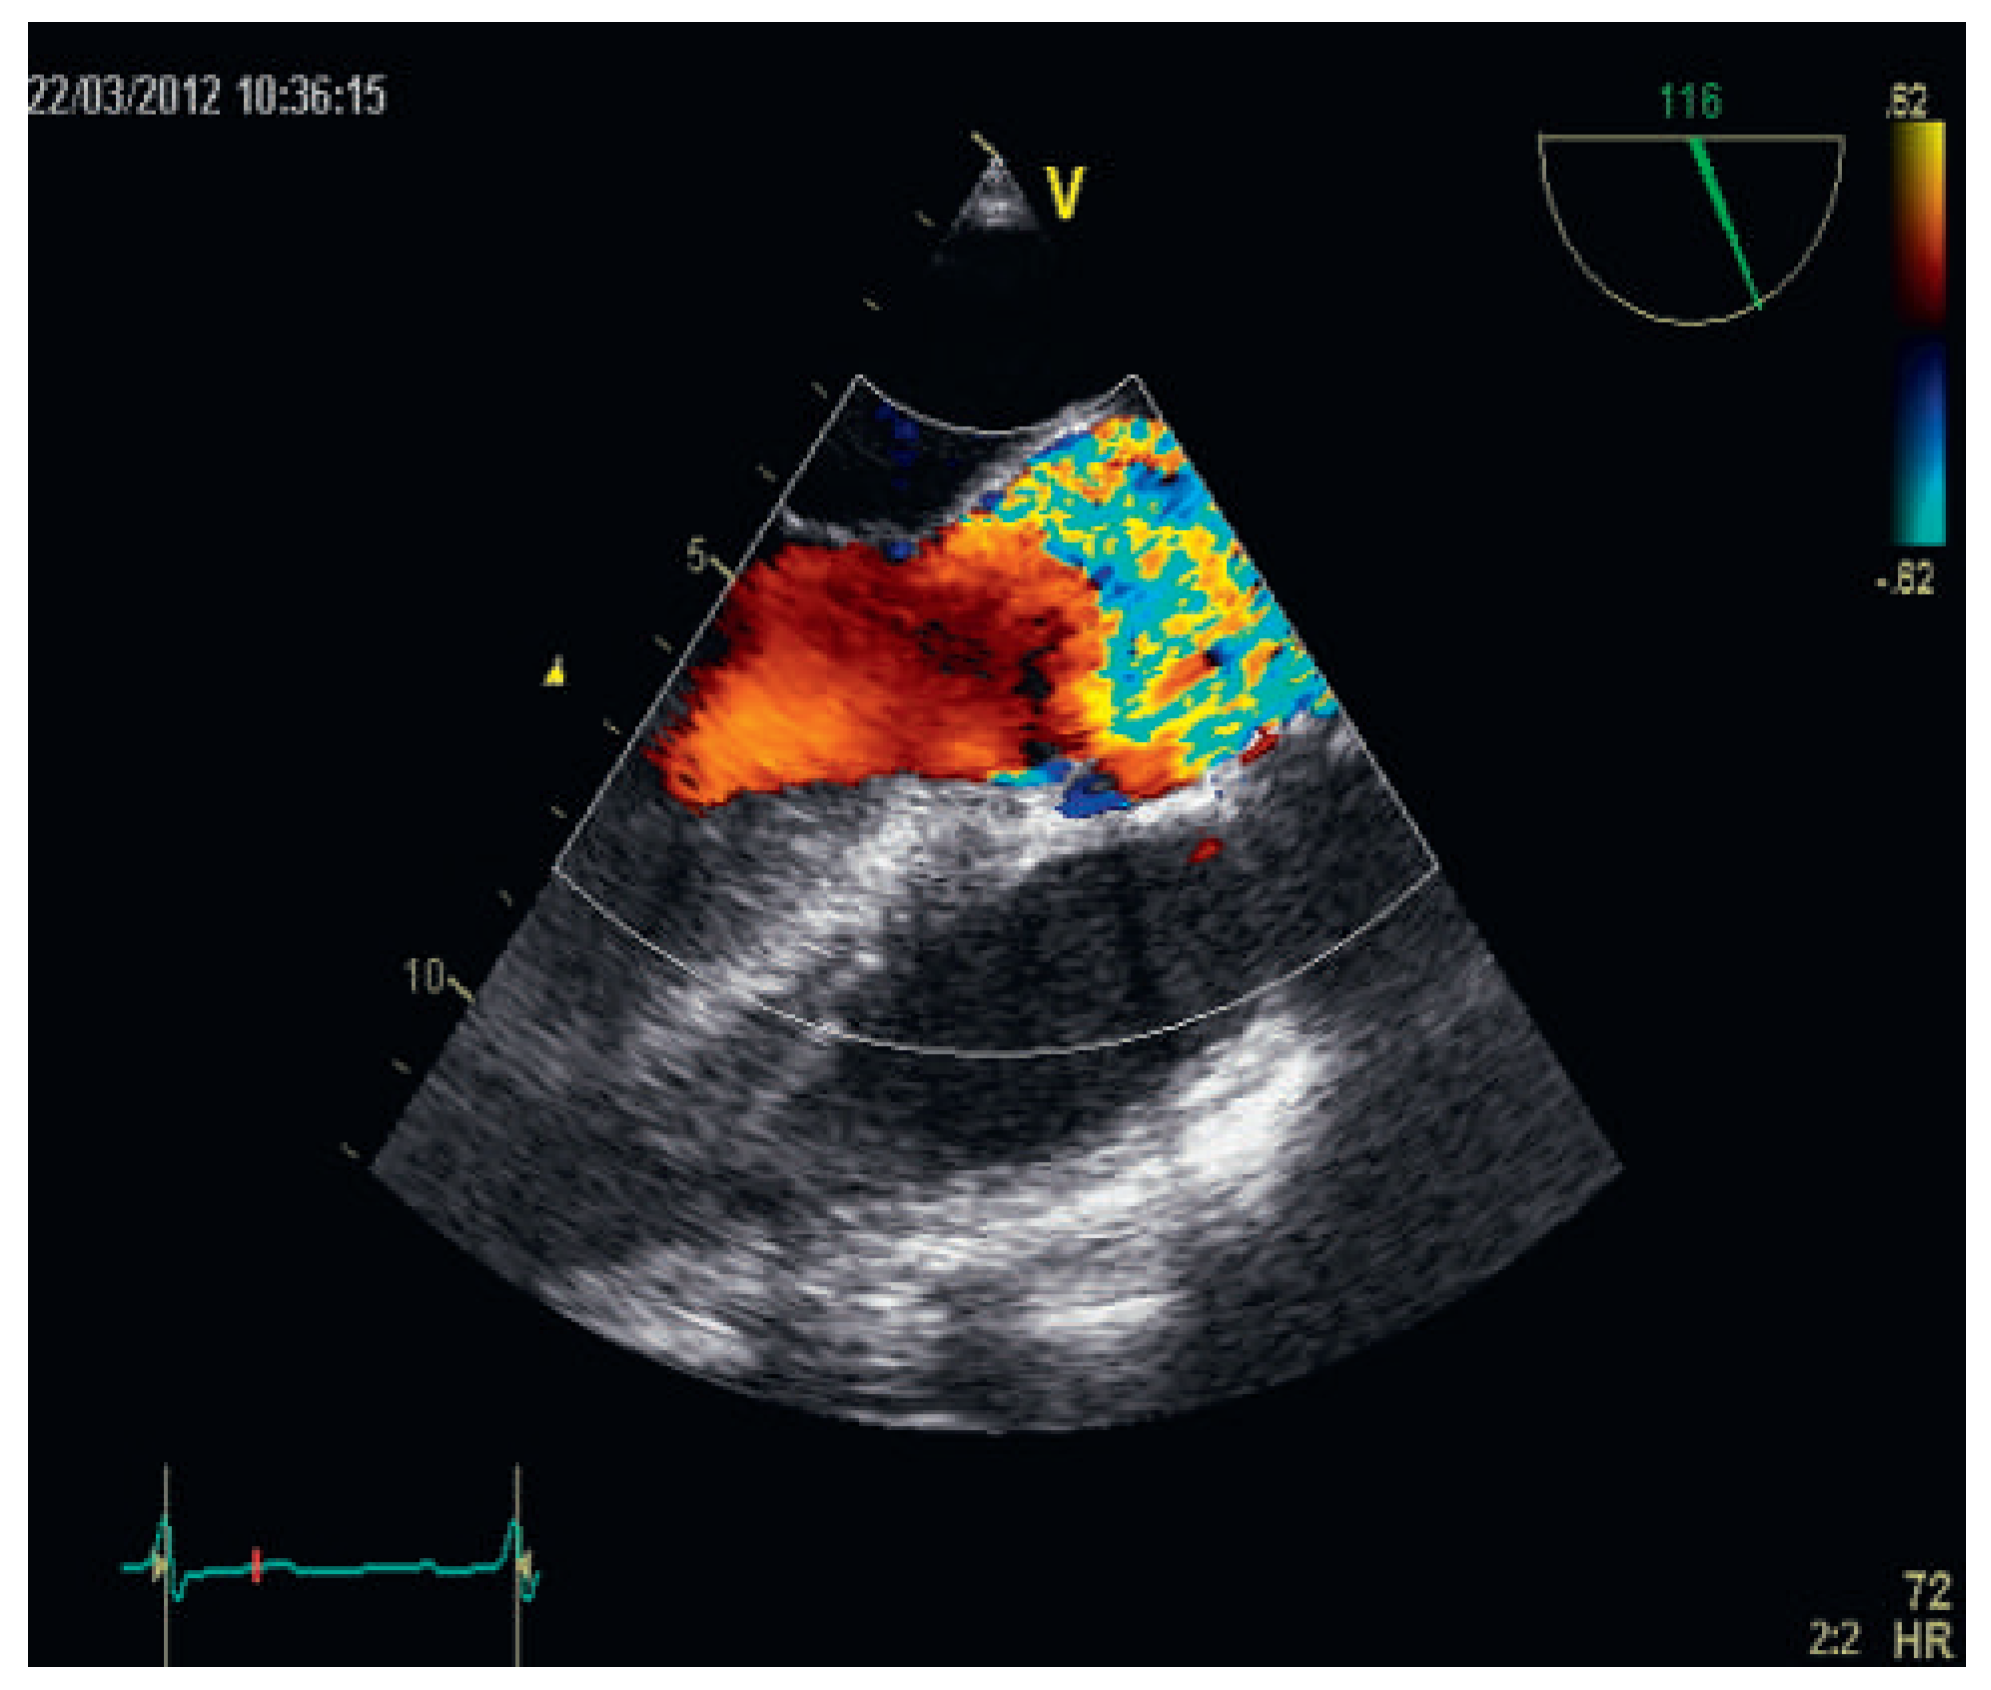

High Doppler-Derived Gradients Across the Aortic Valve May Be Misleading: Potential Causes of Valve Gradient Overestimation